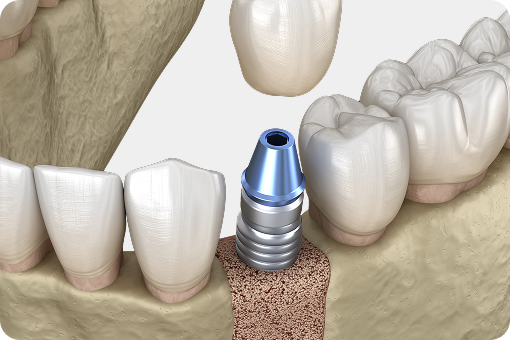

자연치아를 살리는 골든타임,

바로 지금입니다.

자연치아 하나의 가치는 3천만 원 이상,

빠르게 조치할수록 살릴 수 있는 확률은 올라갑니다.